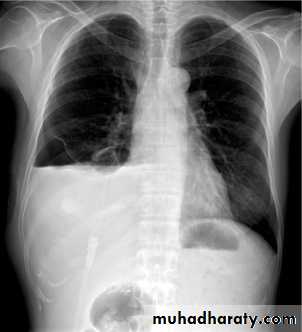

Plain radiographChest radiographs are the most commonly used examination to assess for presence of a pleural effusion, however it should be noted that on a routine erect chest x-ray as much as 250-600 ml of fluid is required before it becomes evident 6. A lateral decubitus film is most sensitive, able to identify even a small amount of fluid. At the other extreme, supine films can mask large quantities of fluid.

Both PA and AP erect films are insensitive to small amounts of fluid. Features include:

blunting of the costophrenic angle

blunting of the cardiophrenic angle

fluid within the horizontal or oblique fissures

eventually a meniscus will be seen, on frontal films seen laterally and gently sloping medially (note:

with large volume effusions, mediastinal shift occurs away from the effusion (note: if coexistent collapse dominates then mediastinal shift may occur towards the effusion)